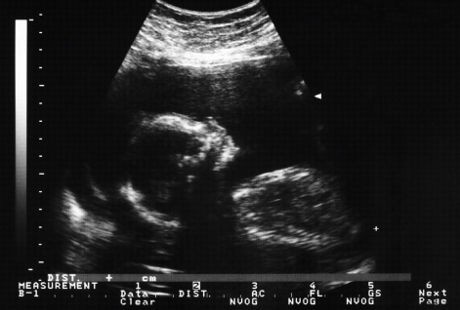

Ilmuwan dari Sun Yat-Sen University dilaporkan jurnal Protein & Cell melakukan rekayasa genetik pada embrio manusia dengan kondisi talasemia, sebuah penyakit bawaan yang disebabkan oleh kecacatan genetik.

Sebanyak 86 embrio yang telah diciptakan untuk bayi tabung oleh ilmuwan di Guangzhou deoxyribose-nucleic acid (DNA)-nya dipotong, diganti, atau dimodifikasi. Bila dibiarkan embrio-embrio tersebut akan dibuang sehingga lewat rekayasa genetik mereka berusaha menghilangkan gen yang bermasalah.